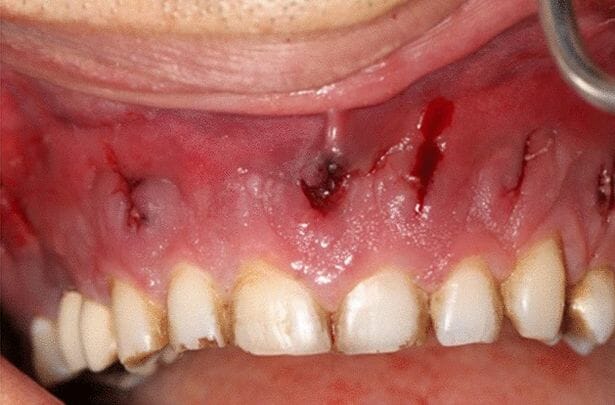

ووفقًا لتقرير نُشر في مجلة Journal of Medical Case Reports، في 3 مارس، تمت إحالة الرجل إلى خبير في التهابات اللثة اكتشف أنه مصاب بعدوى فطرية تأكل اللحم، تُعرف باسم فطار الغشاء المخاطي، تنمو في جزء من فكه السفلي.

وبعد التشخيص المرعب، اكتشف مسعفون من جامعة العلوم الطبية في طهران في وقت لاحق، أن الفطر قد انتشر في أجزاء من تجويفه الأنفي والفم.

وأمضى جراحو التجميل ساعات في إزالة 12 سنًا وعظام الوجه المصابة، لمنع المرض من الانتشار أكثر والتسبب في المزيد من المضاعفات.